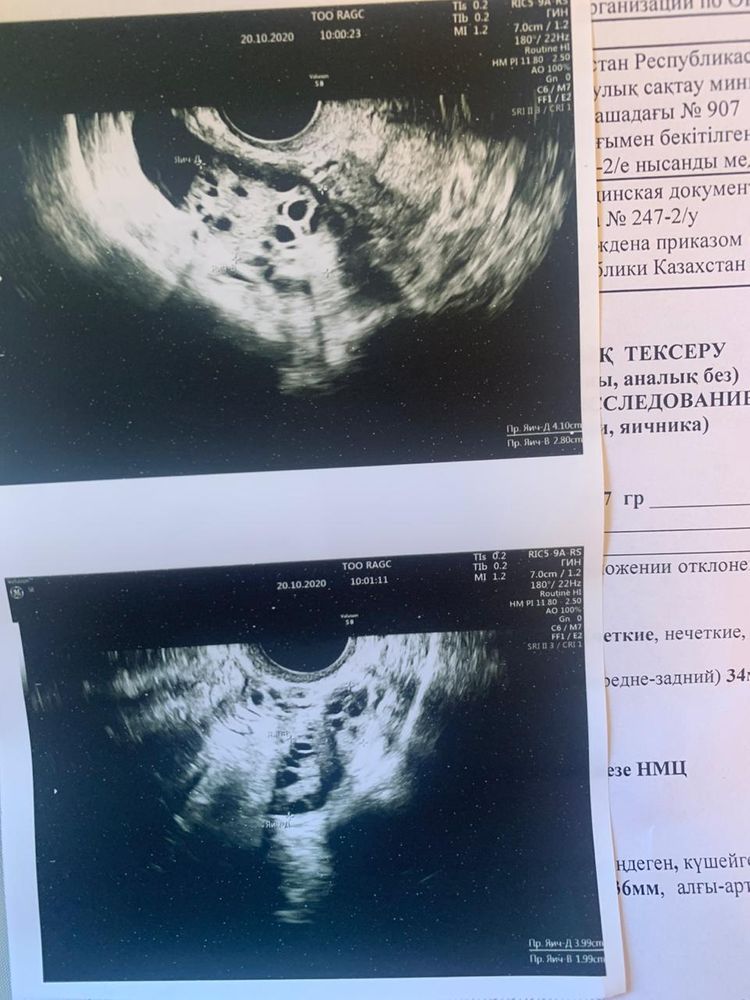

Все привет , у меня поликистоз . Сделали каутерезацию яичников 9 сентября . После этого месячных до сих пор нет . Последние две недели болит и налилась грудь . Неделю назад ходила на узи сказали жёлтого тела нет , в матке тоже ничего не увидели . Эндометрий 11 сказали скоро пойдут месячные . Гин сказал в течение недели . А время уже прошло а их все нет и нет 😭Живот местами тянет , как будто хотят пойти, но не могут . Очень хотим бэбика. Раньше такого не было что при задержке большой сильно болела грудь , тест - . Что это может быть ?

По узи месячные будут не скоро. Идет гормональный сбой. Их надо вызывать искусственно, скорее всего (прогестероном).

узи надо будет переделать. Нет, не исключена, т.к.бывает в жизни всякое!) однако пока тест -, беременности нет.